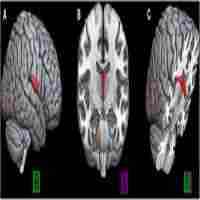

| Abstract | Objective:This study investigated white matter integrity in patients with amnestic mild cognitive impairment by diffusion tensor imaging.Methods:A total of 83 patients with amnestic mild cognitive impairment and 85 elderly healthy controls underwent neuropsychological testing and a diffusion tensor imaging scan. Whole-brain white matter data were parcellated into 50 regions based on the anatomical ICBM-DTI-81 atlas, and regional diffusion metrics consisting of fractional anisotropy, mean diffusivity, radial diffusivity, and axial diffusivity were calculated for each region. Diffusion tensor imaging indices were compared between groups, and it was determined that between-group differences were significantly correlated with neurocognitive performance.Results:Relative to the healthy controls group, the amnestic mild cognitive impairment group exhibited poorer cognitive performance in all neuropsychological tests except the complex figure test (p = 0.083) and showed decreased mean fractional anisotropy in the fornix, increased mean diffusivity in the fornix and bilateral uncinate fasciculus, elevated axial diffusivity in the fornix and genu of corpus callosum, and elevated radial diffusivity in the fornix and bilateral uncinate fasciculus (p < 0.05). Behaviorally, integrity of the bilateral uncinate fasciculus was correlated positively with episodic memory function, while left uncinate fasciculus integrity was positively associated with language function in the amnestic mild cognitive impairment group (p < 0.05).Conclusion:White matter abnormalities in neural pathways associated with memory were correlated with neurocognitive deficiencies in amnestic mild cognitive impairment. Given that amnestic mild cognitive impairment is putatively a prodromal syndrome for Alzheimer’s disease, this study furthers our understanding of the white matter changes associated with Alzheimer’s disease pathogenesis in the predementia stage. |